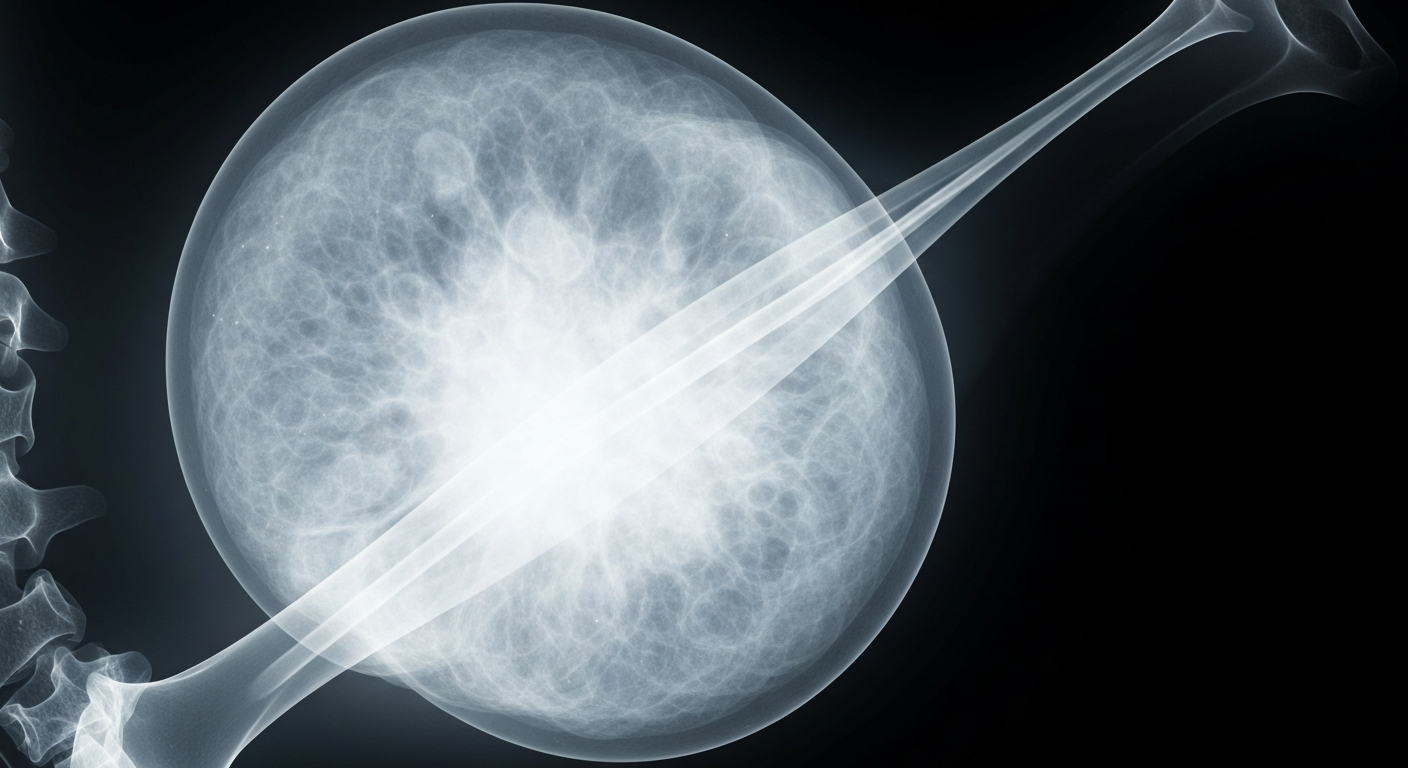

AidaBREAST Multi-Omic Assay Demonstrates Spatial Proteomics for Clinical Oncology

Novel assay developed on Akoya PhenoImager HT platform with Opal chemistry becomes first to predict both locoregional recurrence risk and radiation therapy benefit in early-stage invasive breast cancer.

A groundbreaking new diagnostic tool harnesses the power of spatial proteomics to provide unprecedented insights into breast cancer biology and treatment response.San Francisco TodayPreludeDx and Quanterix Corporation announced that AidaBREAST, the first multi-omic assay to predict both locoregional recurrence risk and radiation therapy benefit in early-stage invasive breast cancer, was developed on the Akoya PhenoImager HT platform using Opal chemistry. This marks a significant milestone in the clinical translation of spatial proteomics. The validation of AidaBREAST included 922 hormone receptor-positive, HER2-negative invasive breast cancer patients across four academic and clinical centers in the United States and Sweden, with a median follow-up of ~10 years.

AidaBREAST leverages spatial biology and AI to provide unique insights into the tumor and immune-microenvironment, giving oncologists a tool that can not only predict a patient's likelihood of recurrence, but also whether radiation therapy will benefit that specific patient. This represents a meaningful shift in how treatment decisions can be informed.

The AidaBREAST assay integrates spatial multiplex protein expression data obtained using the PhenoImager HT platform and Opal chemistry, with targeted next-generation RNA sequencing, to provide a comprehensive assessment of tumor biology. This approach enables the assay to be both prognostic for 10-year locoregional recurrence risk and predictive for radiation therapy benefit, capabilities not previously available in a single test for early-stage invasive breast cancer.